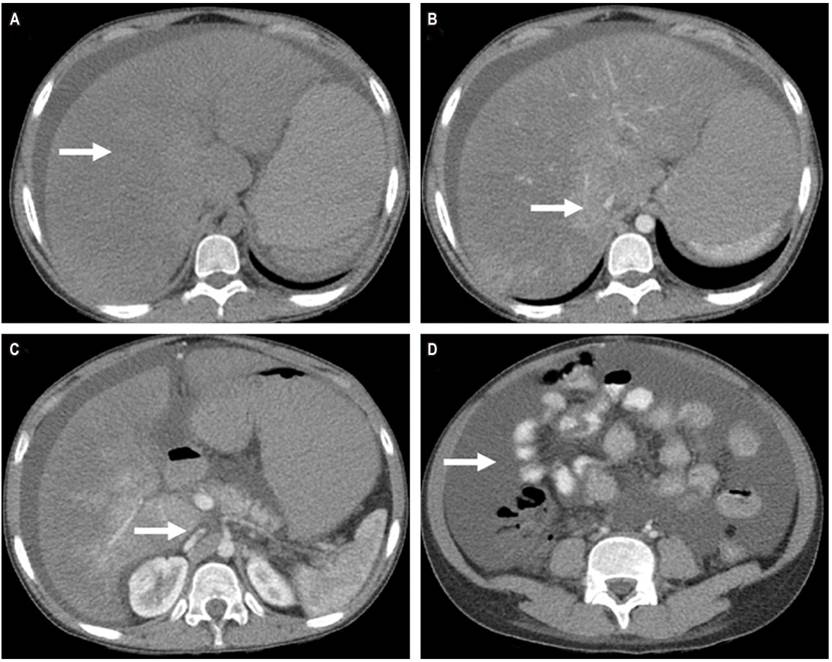

Physical examination found that the whites of her eyes were jaundiced, and she had ascites and a palpable hepatomegaly four centimeters from the right costal edge. Digestive endoscopy showed hypertensive gastropathy and esophageal varices grade II. They were ligated endoscopically. She required paracentesis twice to evacuate ascitic fluid (5,000 and 7,000 mL) which had a high albumin gradient. The Doppler study of hepatic circulation showed an absence of flow in the suprahepatic veins. An abdominal CT scan showed portal hypertension (collateral circulation and ascites) with extensive thrombosis of the suprahepatic veins and hepatomegaly compressing the vein cava (Figure 1). This confirmed the diagnosis of subacute postpartum Budd-Chiari syndrome. Laboratory studies are described in Table 1. The Rotterdam score, a prognostic index for Budd-Chiari syndrome, was 1.16 which placed her at intermediate risk. Studies were extended in search of thrombophilia to explain the etiology of the clinical picture, but none of these tests were positive. This confirmed the causal relationship between the hypercoagulable state of the puerperium as and Budd-Chiari syndrome. We considered that the use of medroxyprogesterone had probably enhanced the thrombotic condition.

Figure 1 CT scan of the abdomen and pelvis. A. Phase without contrast shows hepatomegaly. B. Contrasted phase shows absence of suprahepatic vein flow. C. Contrasted phase shows compression of the inferior vena cava. D. Contrasted phase shows ascites.